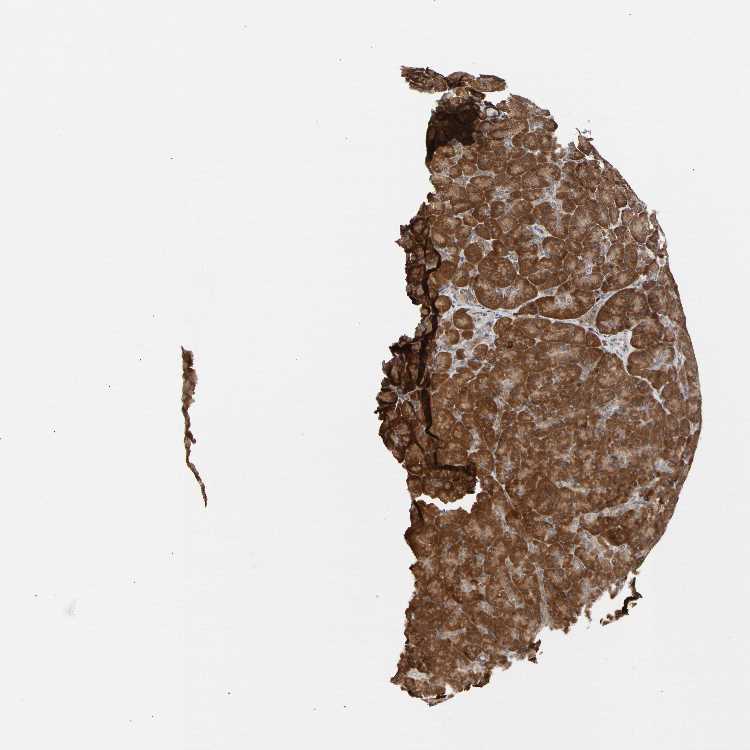

PANCREAS - Antibody stainingi

Antibody staining in the annotated cell types in the current human tissue is reported as not detected, low, medium, or high, based on conventional immunohistochemistry profiling in selected tissues. This score is based on the combination of the staining intensity and fraction of stained cells.

Each image is clickable and will lead to virtual microscopy that enables deeper exploration of all samples and also displays staining intensity scores, fraction scores and subcellular localization as well as patient and tissue information for each sample.

Antibody HPA007191

Exocrine glandular cells High

Pancreatic endocrine cells Medium